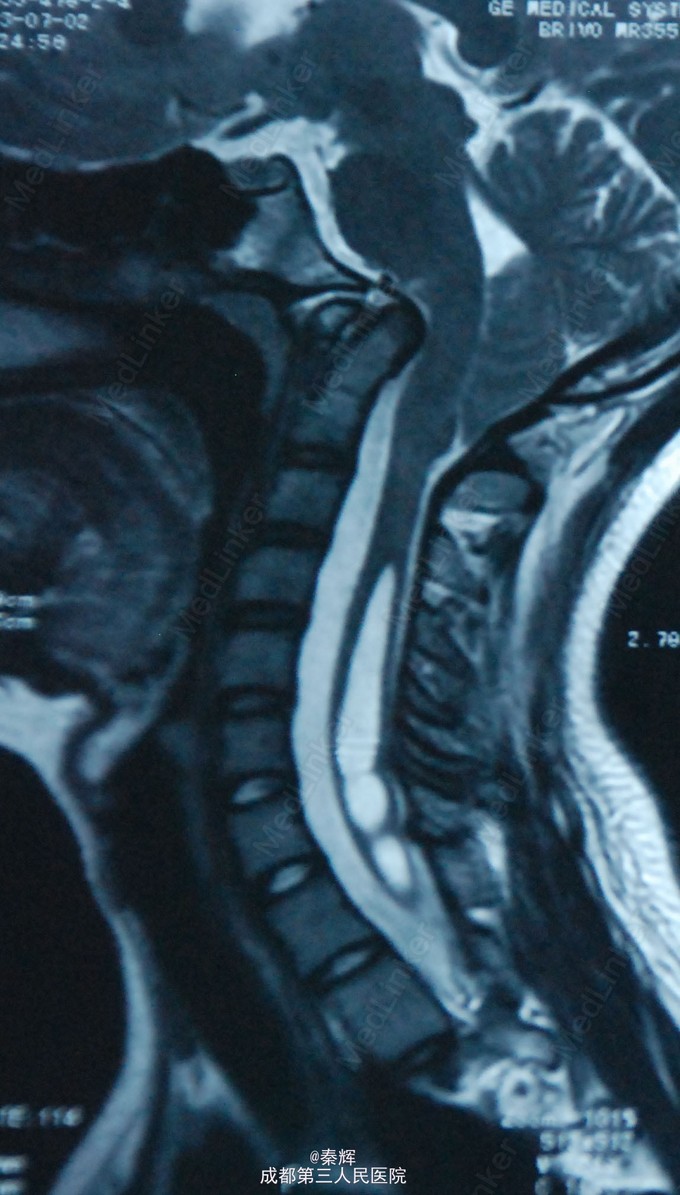

患者女,15岁,半年前反复出现头晕、行走不稳。

四肢肌张力增高,腱反射亢进,共济失调。X片、MRI等检查后诊断“颅底凹陷、脊髓空洞”。

诊断“颅底凹陷、脊髓空洞”,行牵引复位、枕骨大孔扩大、枕颈融合、内固定术。

术后半年复查症状缓解。 颅底凹陷症是以枕骨大孔为中心的颅底骨组织、寰椎及枢椎骨质发育畸形,寰椎向颅腔内陷入,枢椎齿状突高出正常水平进入枕骨大孔,使枕骨大孔狭窄,后颅窝变小,从而压迫延髓、小脑及牵拉神经根产生一系列症状,或有椎动脉供血不足表现,可同时伴有脊髓空洞。